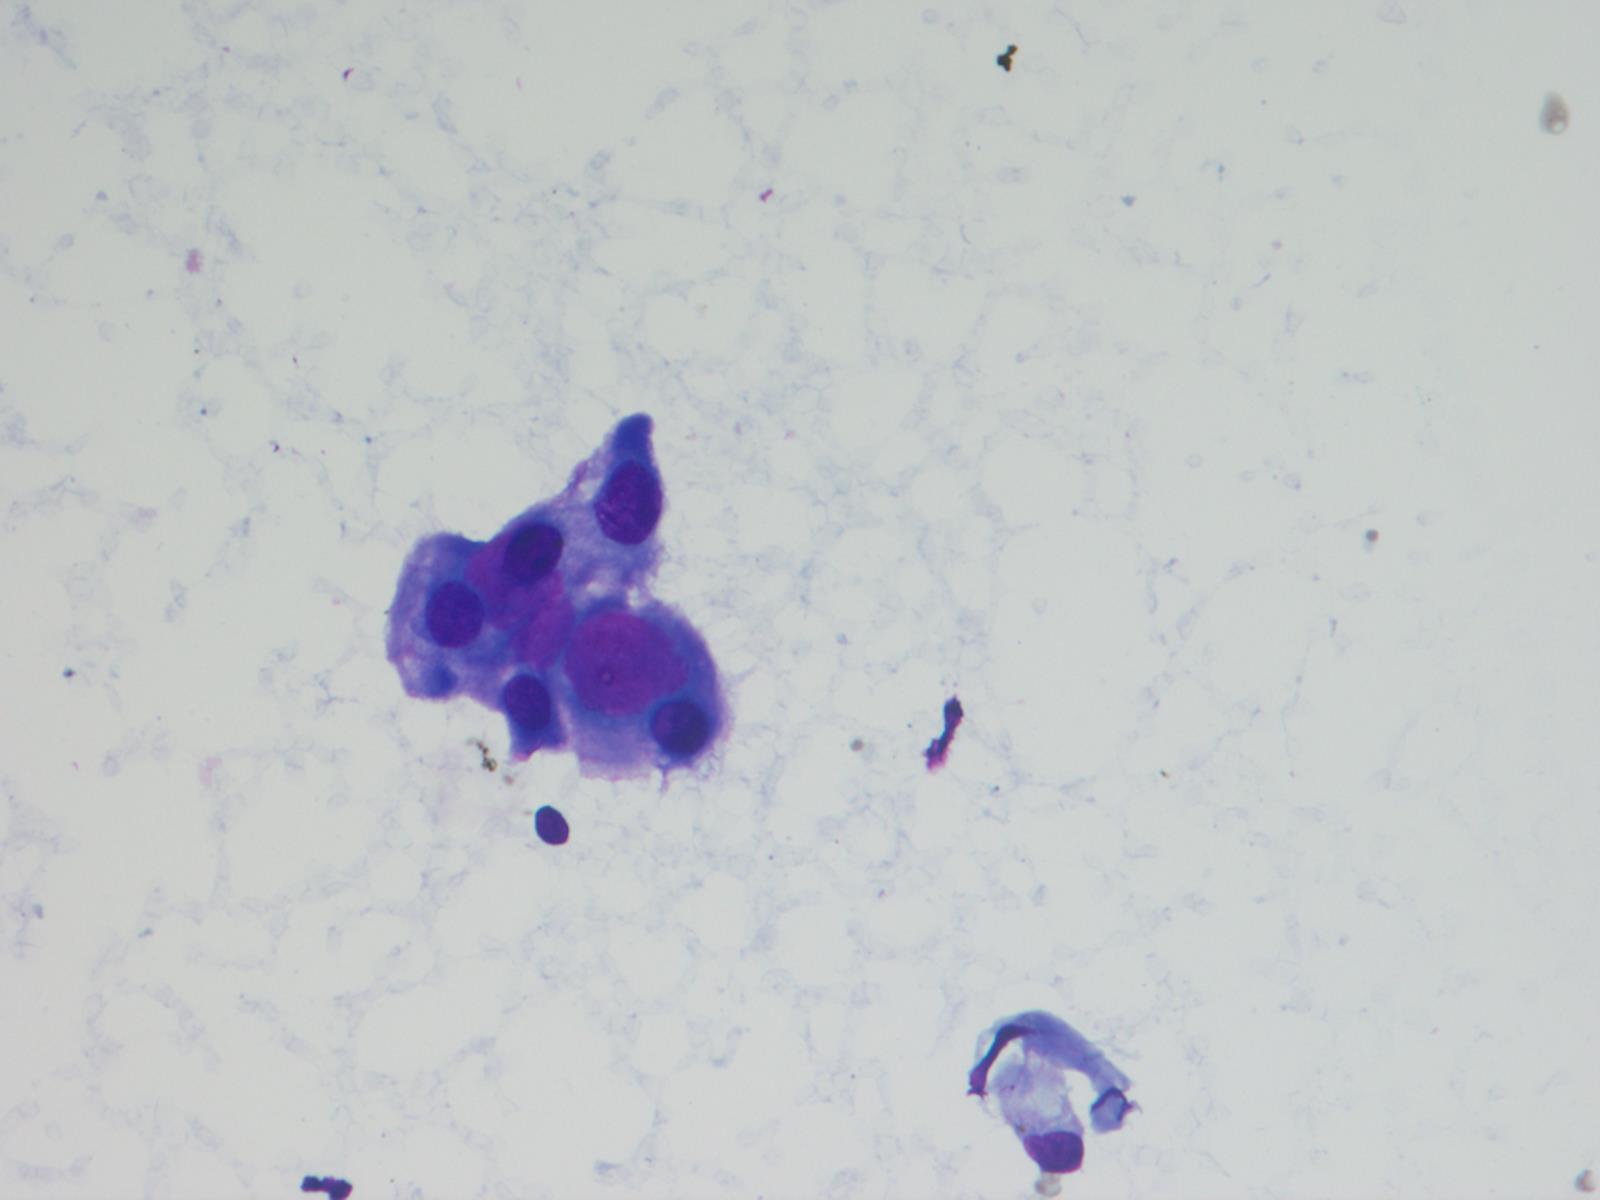

Frozen section description

- Intraoperative squash / smear preparation and frozen section reveals epithelioid to spindled tumor cells arranged around microcysts and forming papillary structures with perivascular myxoid change; these features are diagnostic in the appropriate clinical setting

Cytology description

- Cytology usually recapitulates the histologic findings; myxoid matrix and cells show nuclear uniformity and process formation

- Epithelioid to spindle cells

- Arrangement of tumor cells around blood vessels forms papillary structures with perivascular myxoid change

- Tumor cells are arranged around myxoid microcysts

Cytology images